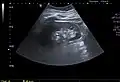

Renal ultrasonography of a simple renal cyst with posterior enhancement.

Renal cyst as seen on abdominal ultrasound